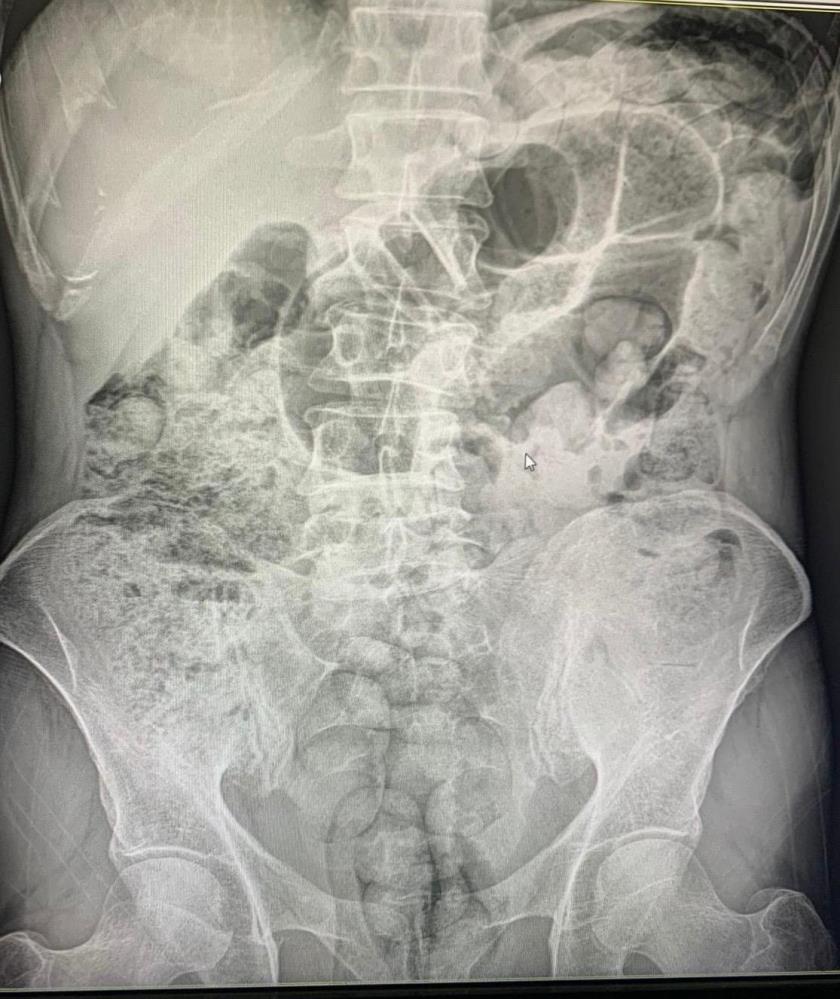

Siirt'te 4 kişinin midelerindeki 1 kilo 597 gram uyuşturucu madde, 10 günlük hastane sürecinin ardından cerrahi müdahaleyle çıkartıldı. Şahıslar çıkarıldıkları mahkemece tutuklandı.

Şahısların midelerinde bulunan uyuşturucu maddeler 10 gün devam eden hastane süreci sonucunda cerrahi yöntemler kullanılarak çıkartıldı.

Şüpheli şahısların midelerinden 119 paket halinde 1 kilo 597 gram uyuşturucu madde çıkartıldı. Zanlılar, sevk edildikleri adli makamlarca tutuklanarak cezaevine sevk edildi.